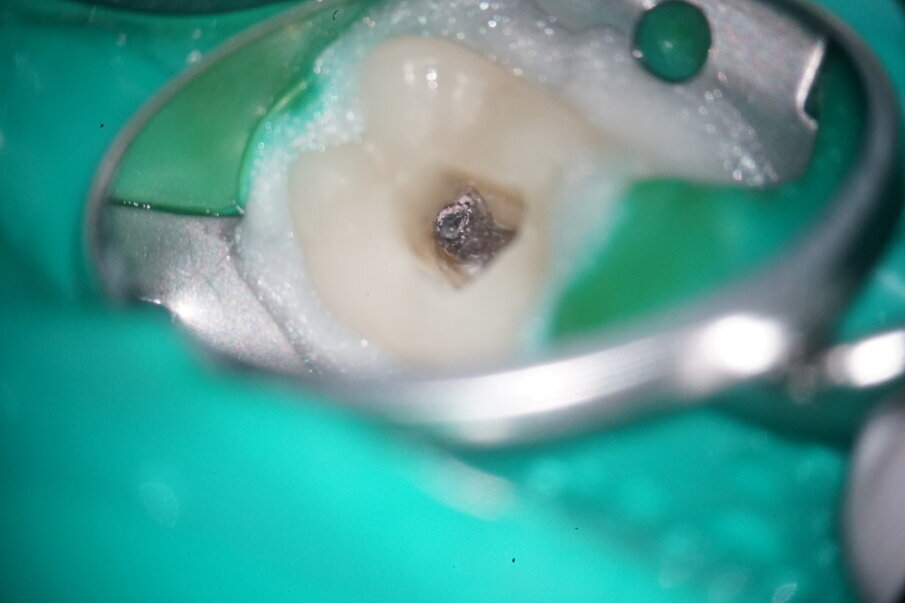

An 87-year-old female patient was referred to our clinic with pain in the third quadrant. The clinical and radiographic examination (using single-image radiography and CBCT) confirmed the suspicion of symptomatic periapical periodontitis at tooth #36 (Fig. 1). The preoperative single image suggested that a carrier-based root canal filling material had been used; furthermore, two ledges were visible in the mesial canal system. In addition, a second distal canal had to be assumed.

After applying the dental dam and preparing the access cavity, the next step was to remove the existing obturation material (Figs. 3 & 4). A high-speed rotary HyFlex Remover was used for this purpose (Fig. 5). The revision file efficiently removed the materials from the root canal so that additional solvent could be dispensed with during treatment. Unlike in other cases, the plastic carriers in this case were not extracted with an aid, but were machined (see video above). The non-cutting tip of the retreatment file protects the surrounding tooth structure during this procedure, which makes handling even easier.

Fig. 3: Initial situation of mesial canals.